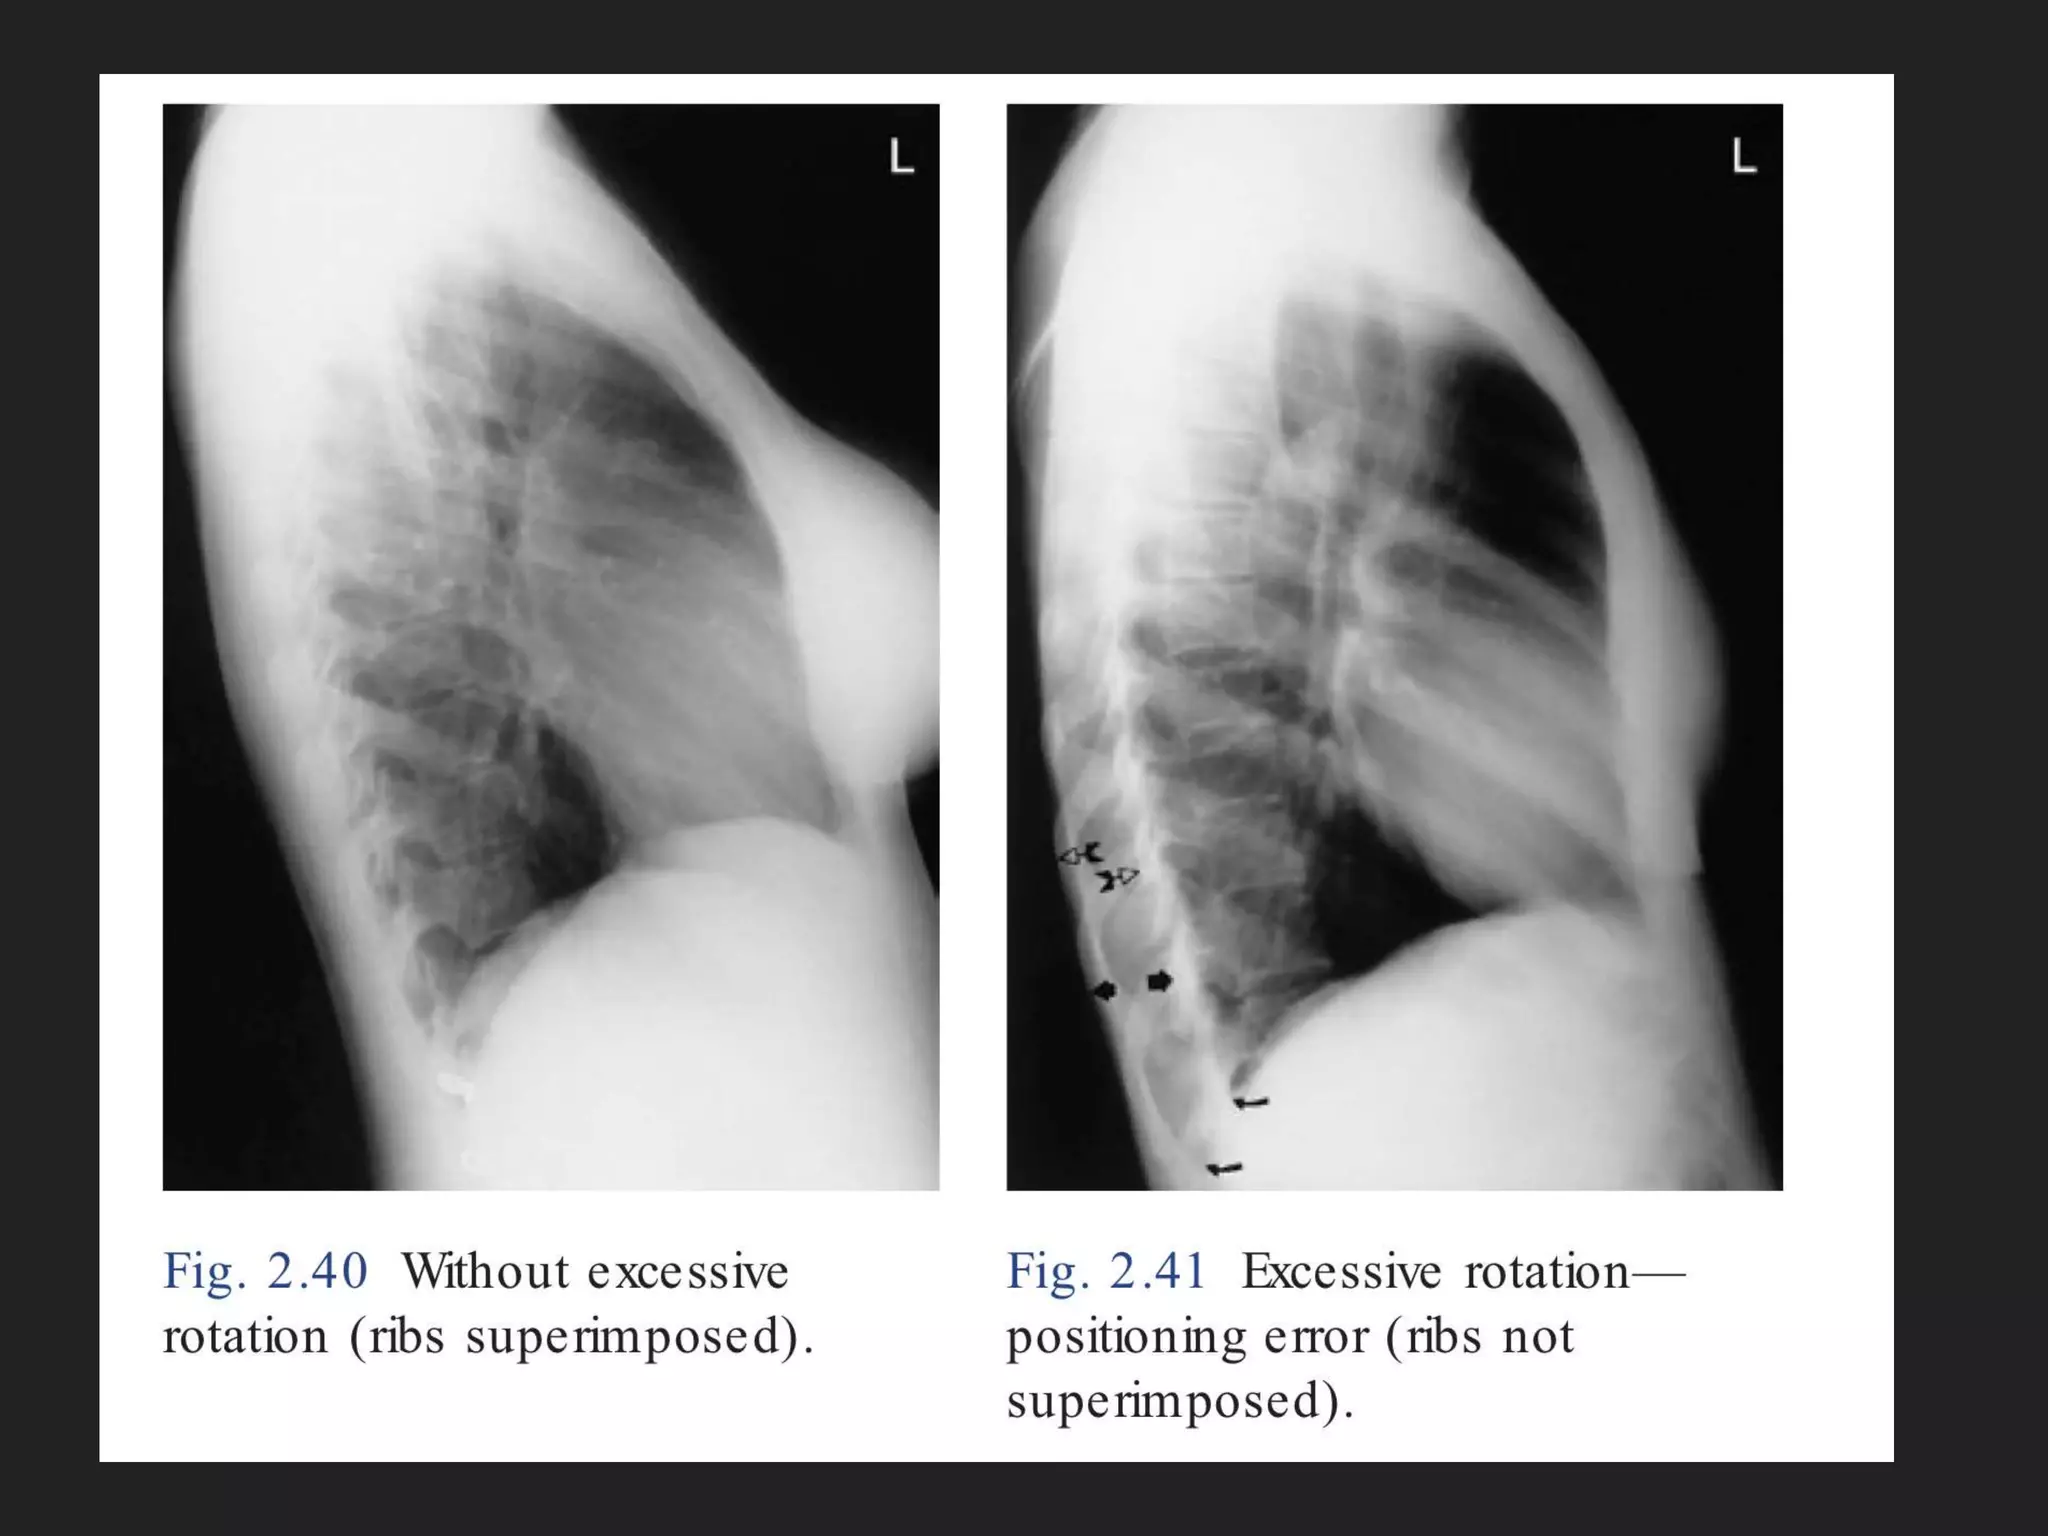

The document provides detailed instructions for performing a chest x-ray, emphasizing proper patient positioning and technical requirements for optimal image quality. Key points include centering the trachea, ensuring full inspiration, and visibility of specific anatomical features. Additionally, it outlines collimation margins and patient stance to achieve a clear view of lung fields.